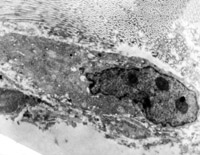

5-2-2 傷后第1天,毛細血管內(nèi)皮細胞核固縮,管腔內(nèi)血液凝集和瘀滯  TEM×6000